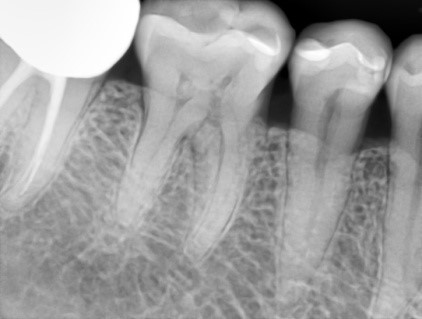

Основной целью исследования с помощью цифровой внутриротовой рентгенографии является получение четкого, ясного изображения, как зубов, так и периапикальных тканей. (Рис.1) При периапикальной контактной рентгенографии, необходимо помнить, что при интерпретации изображения профессионалами учитывается тени деструктивных изменений периапикальных зон, которые наслаиваются на контуры корней зубов, при этом искажаются размеры. Такие недостатки напрямую зависят от погрешности наклона рентгеновской трубки, центрации пучка излучения, локализация пленки в полости рта пациента. Современные лучевые технологии в стоматологической практике постоянно в процессе совершенствования. С целью использования всех возможностей методов рентгенодиагностики при максимальном уменьшении лучевой нагрузки во время проведения исследования, фирмы-производители предлагают огромный выбор рентгенотехники на стоматологическом рынке. Выбор наиболее совершенных технических данных, основывается на качестве изображения, скорости его получения и передачи, совместимости с любым компьютером, долговечности и эргономичности, легкости использования, а также цене. Ценность EzSensor от Vatech заключена в уникальном дизайне датчиков: тонкий корпус с гладкими краями (Рис.2), укрепленное кабельное соединение. Для гарантийного попадания лучей на датчик EzSensor в полости рта разработаны позиционеры RINN (Рис.3) для разных типов зубов и типов съемки. Эта функция привносит удобство в работу стоматолога и гарантирует легкость позиционирования, на ряду с комфортабельностью для пациентов.

Качество снимков обладает высокой разрешающей способностью отношение сигнал /шум – важнейший фактор в получении изображения, составляет >37 dB, размер пикселя 0,035 мм. Благодаря высокой чувствительности и вариабельности размеров датчиков, визуализация становится детальной, в этой связи возможно проведение диагностики кариеса на контактных поверхностях. Преимущества данной методики при сравнении с пленочной рентгенографии состоит в скорости получения изображения объекта исследования, низкая доза облучения пациентов, возможность постпроцессорской обработки, визуализации деталей в диагностике послеоперационных результатов дентальной имплантации, эндодонтического лечения и постэндодонтического лечения (Рис.5), уточнения расположения кист, гранулем, конкрементов в протоках слюнных желез.

Рис. 5 Диагностика дентальной имплантации и эндодонтичского лечения.